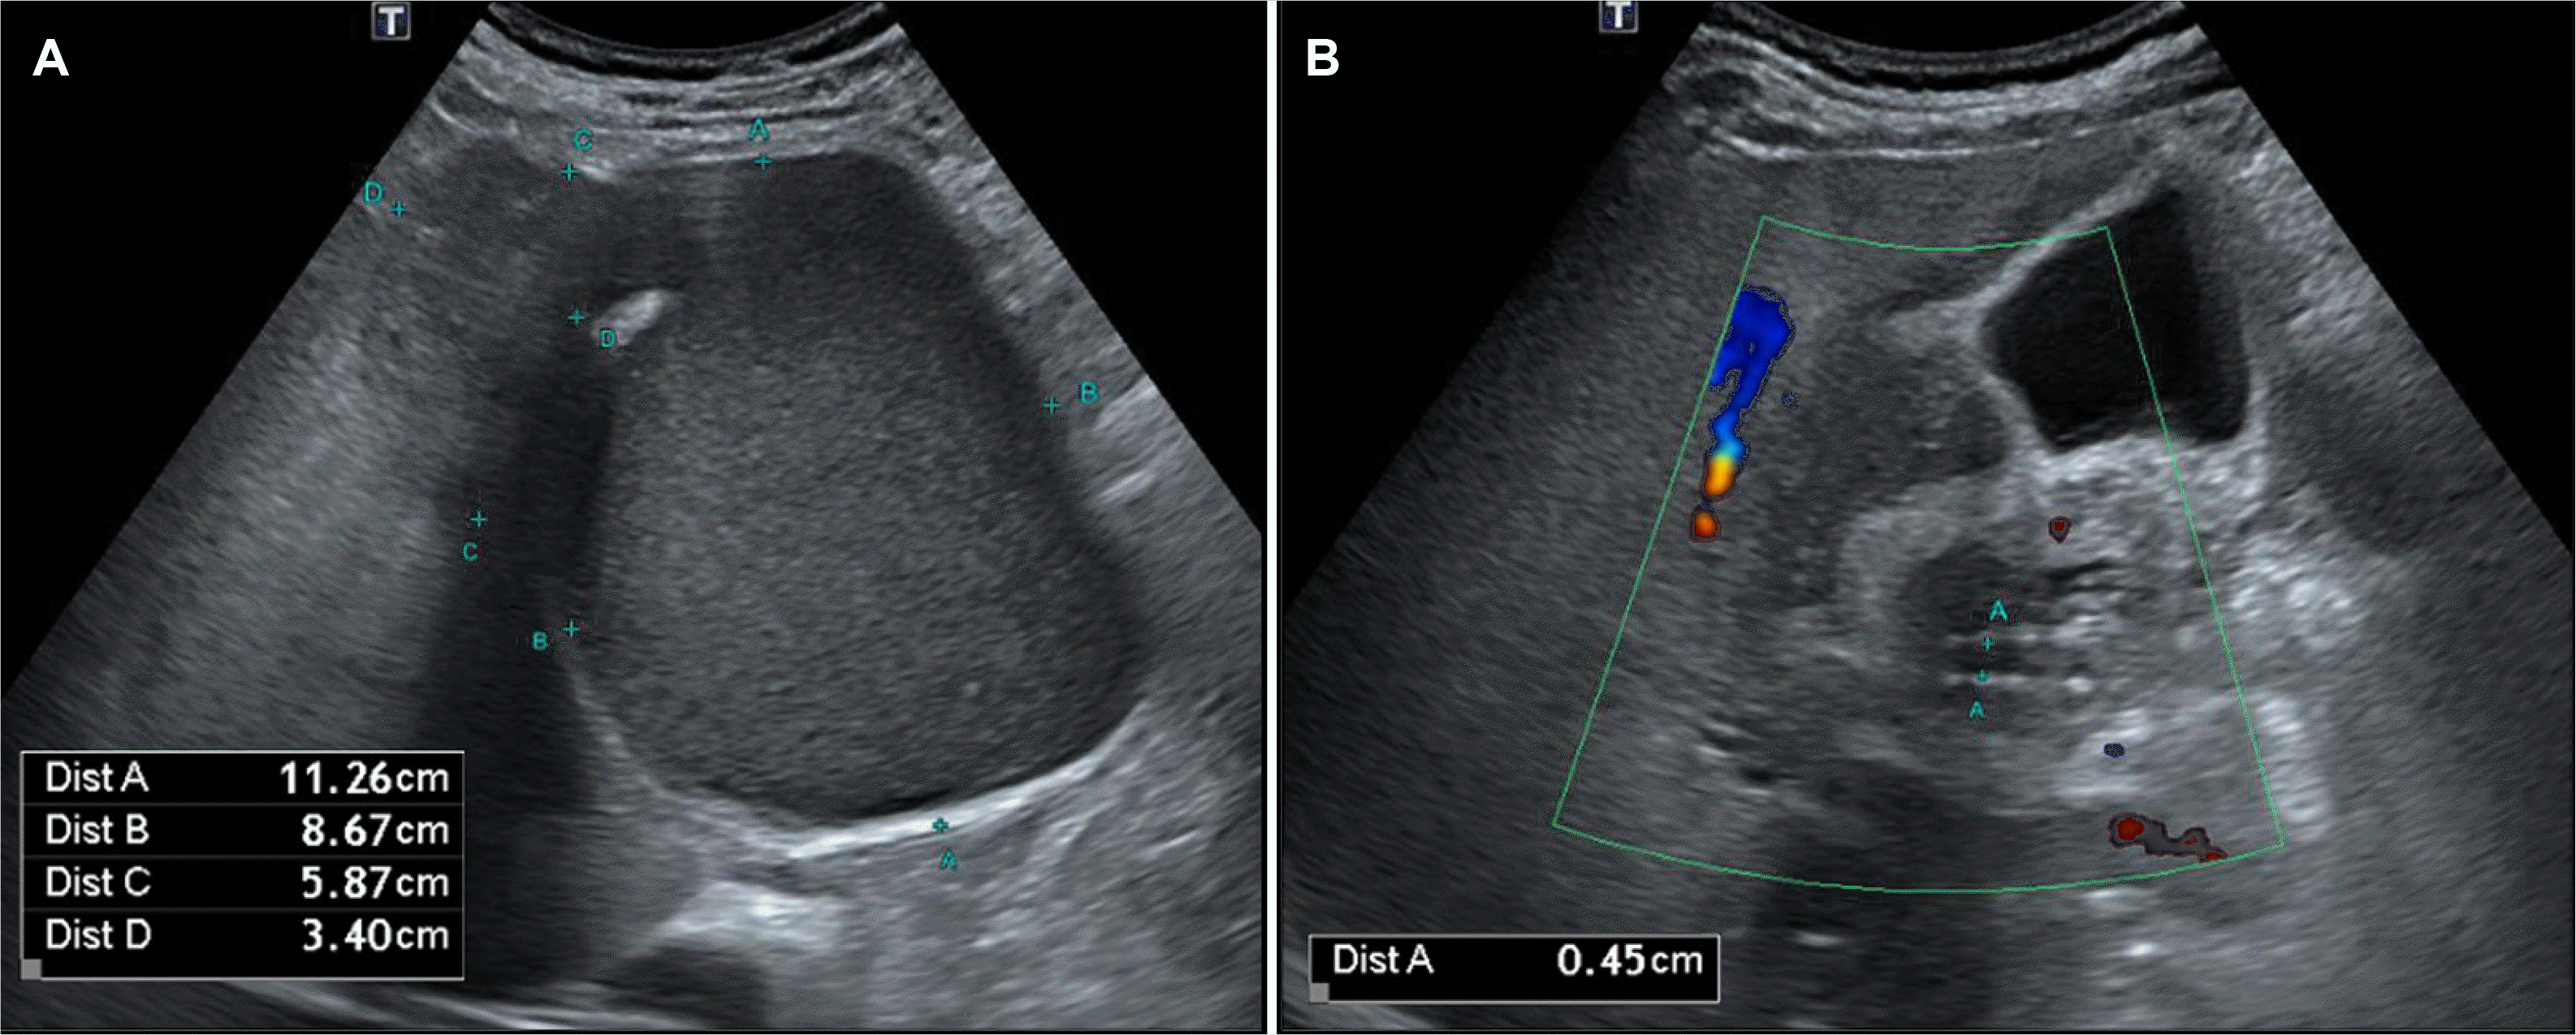

Fig. 1

Transabdominal US image obtained in a 62-year-old man shows (A) two hypoechoic lesions and (B) mixed-echogenicity lesions without biliary dilatation.